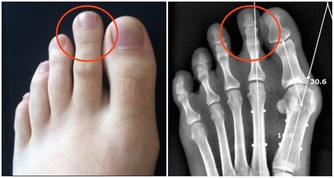

5、尿液混濁有泡沫現在是夏季,又到了喝水的季節,因為大量的汗液排除,所以喝水成為了最簡單而方便的解暑方式。而喝的水中海油一部分會通過尿液排除,所以尿液的清澈與否以及泡沫的多少都是很直觀的判斷腎臟的健康狀況。而腎臟一旦出現問題,就會與腎炎、腎結石、腎功能衰竭等疾病直接相關,嚴重的甚至會威脅生命。若小便泡沫突然變多,長時間不消失,說明尿液中排泄的蛋白質較多,尿液顏色異常,呈濃茶色、醬油色或混濁如洗米水時。都應引起重視,這些都說明你的腎臟出現了問題。6、早起身體會出現浮腫我們每天都需要喝大量的水來滿足身體的需要,因為身體的新陳代謝都需要水的參與,而這麼多的水到身體中都會經過哪裡呢?腎臟是人體代謝水分的器官,腎臟好的人,整個人的泌尿系統也會很健康的循環,腎不好,水就會蓄積,尤其是在早上很容易出現浮腫的現象。例如:我們晚上要是大量的喝水,就會加重腎臟的負擔,第二天容易在眼睛周圍出現水腫的癥狀。所以我們正常的飲水的情況下,如果還會經常出現早起眼皮浮腫,或者腳、腿的浮腫,都說明你的腎臟可能出現了問題了。